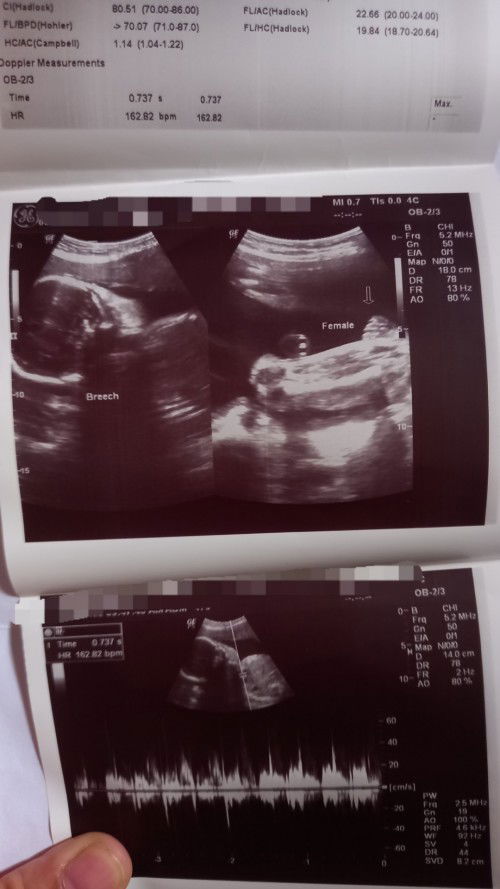

Good morning po mga mommies, tatanong ko lang kung malinaw po bang girl ang gender. Thank you

Di po masyadong clear pero mukhang burger